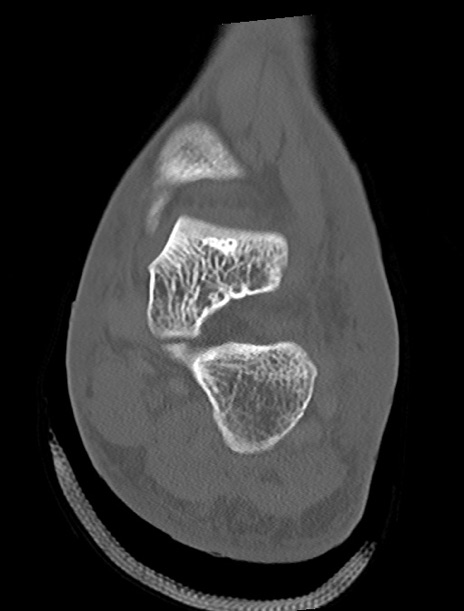

症例37 左足関節CT(冠状断像)

左足関節CT

横断像